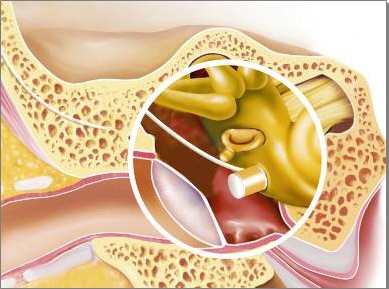

A kérgi mastoidotomy működik a vágási vágó hagyományos határok antrumból nyitás. Következő mastoidotomy továbbra is használja az operatív mikrosokpa, maró- és gyémánt. Amikor vezetőképes és vegyes halláscsökkenés, FMT merőleges a kerek ablak membránján és fascia bezáródik (4. ábra).

4. ábra - a helyét a FMT